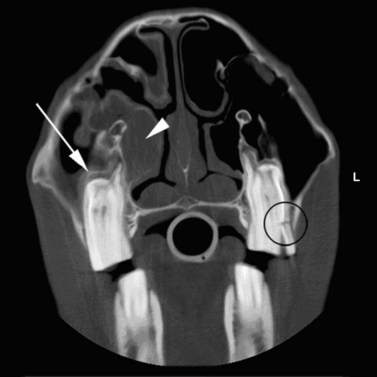

Fig. 13.43 Radiograph (A) and CT images (B and C) of a compound odontoma in a 2-year-old TB colt.

(Images courtesy of J. Easley.)